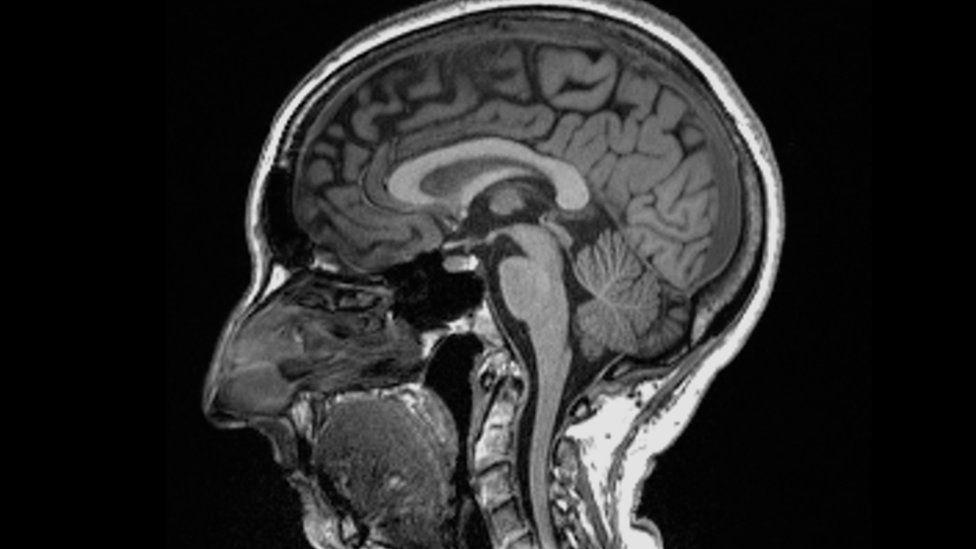

Africa-Press – Namibia. Catching Covid may cause changes to the brain, a study suggests. Scientists found significant differences in MRI (magnetic resonance imaging) scans before and after infection.

Even after a mild infection, the overall size of the brain had shrunk slightly, with less grey matter in the parts related to smell and memory. The researchers do not know whether the changes are permanent but stressed the brain could heal. The study is published in the journal Nature.